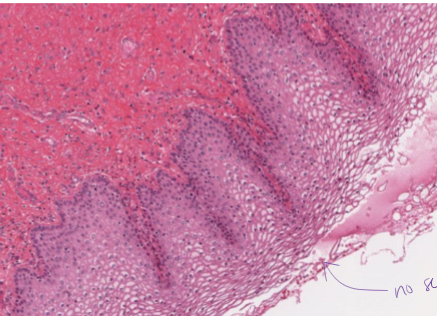

what is this?

stratified squamos epthitelial, keratinized

What is stratified squamous ET, keratinized?

2+ later squamous cells with keratin on apical side (no nuclei in keratin)

found on skin

surface cells are squamos

protective